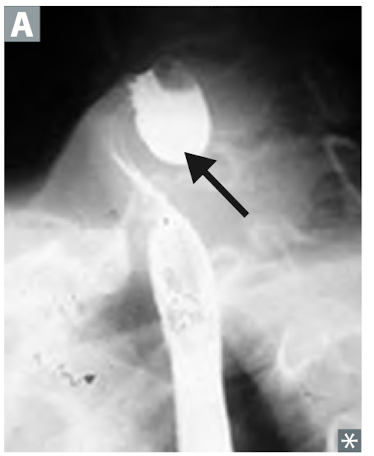

16

Q

What can you see on barium swallow in a patient with CRC?

A

“Apple core” lesion on X-ray